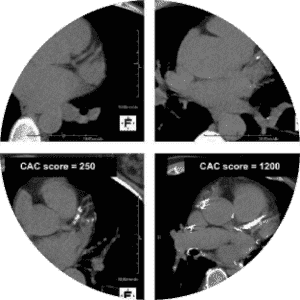

Over the past several years I have focused on empowering patients both with education and real-time biofeedback. In our office, we have embraced the use